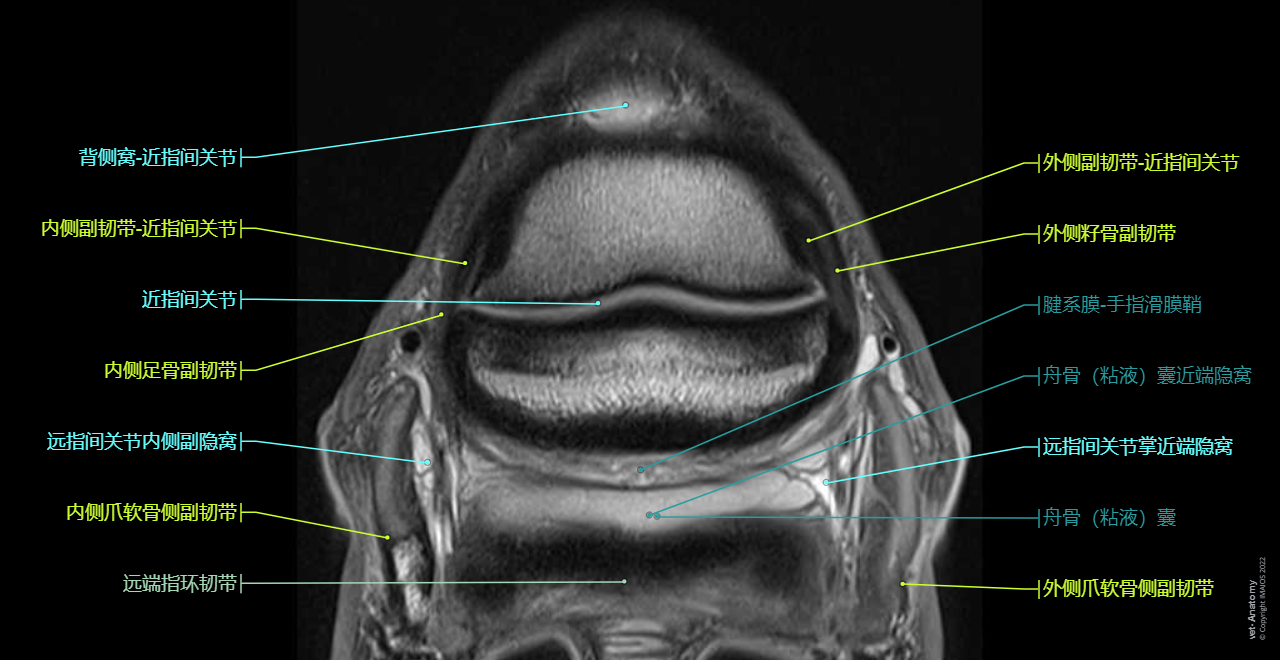

Anatomy of the equine digit on Magnetic Resonance Imaging (MRI): Superficial digital flexor tendon [SDFT], Common digital extensor tendon, Deep digital flexor tendon [DDFT], Proximal interphalangeal joint [Pastern joint; PIP joint], Distal interphalangeal joint [Coffin joint; DIP joint]